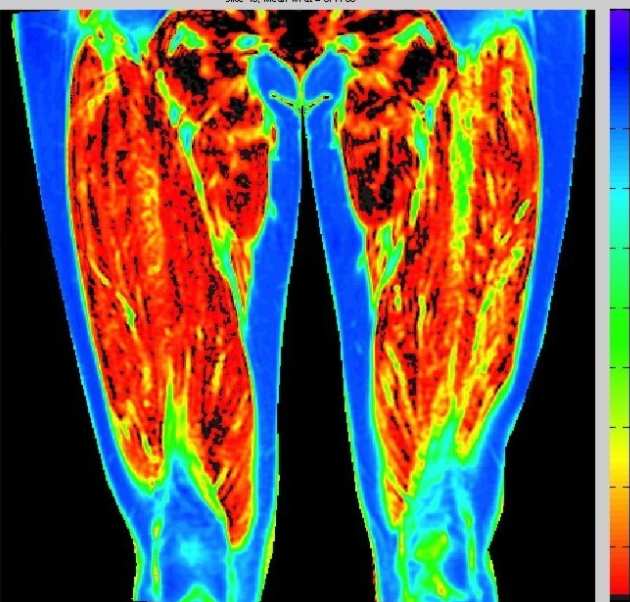

Muscle changes post ACLR

We are using a number of MRI measurements at Stanford University to investigate thigh muscle changes post ACL reconstruction. We aim to develop a measure of muscle quality to assess early changes after surgery with different grafts.

We are using a number of MRI measurements at Stanford University to investigate thigh muscle changes post ACL reconstruction. We aim to develop a measure of muscle quality to assess early changes after surgery with different grafts.